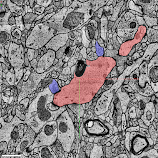

H01 样本通过连续切片电子显微镜,以 4 纳米分辨率成像,利用自动计算技术进行重建和标注,然后进行分析,从而获得对人类大脑皮层结构的初步了解。该数据集由大约一立方毫米大脑组织的成像数据构成,其中包括数万个重建的神经元、数百万个神经元片段、1.3 亿个标注的突触、104 个经过勘校的细胞,以及许多其他的亚细胞标注和结构,所有这些都可以通过 Neuroglancer 浏览器界面轻松访问。迄今为止,H01 是所有物种中根据这种详细程度成像和重建的最大的脑组织样本。其也是对人类大脑皮层中突触连接的第一次大规模研究。其中突触连接跨越了大脑皮层中各层的多种细胞类型。这个项目的主要目标是为研究人脑提供一种新资源,改进并扩展基础连接组学技术。

这些大约 5300 个物理切片的成像产生了 2.25 亿个独立的 2D 图像。然后,我们的团队通过计算,对这些数据进行拼接和对齐,从而生成一个单独的 3D 样本。虽然数据的质量普遍极好,但这些对齐流水线必须有效地应对一系列挑战,包括成像伪影、缺失部分、显微镜参数变化以及组织的物理拉伸和压缩。对齐之后,我们会应用多尺度泛洪填充网络流水线(使用数千个 Google Cloud TPU)生成组织中每一个细胞的 3D 分割。我们还会应用其他机器学习流水线来识别和描绘 1.3 亿个突触,将每个 3D 片段分类为不同的“子部分”(如轴突、树突或细胞体),并识别其他感兴趣的结构,如髓鞘和纤毛。

H01 样本:1.4PB 量的图像捕获了大约一立方毫米的人脑组织

样本涵盖了全部六层大脑皮层

Neuroglancer 界面中的 H01 样本和注释。用户可以根据所在层和类型选择特定的细胞,查看该细胞的传入突触和传出突触,以及更多其他部分